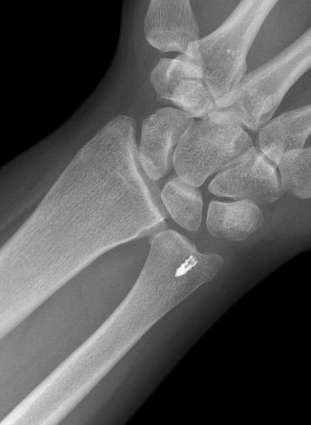

Isolated dorsal dislocation DRUJ

Isolated dorsal DRUJ instability with ulna sided TFCC tear

Xray

True lateral

- radial styloid overlies proximal scaphoid / lunate / triquetram

Dorsal subluxation of the distal ulna

CT